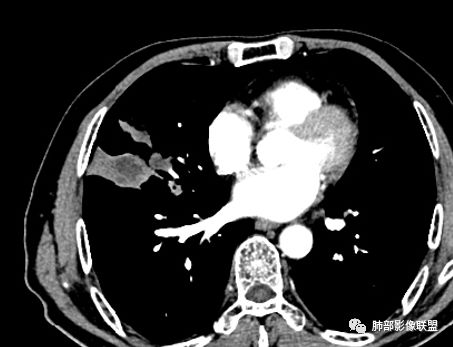

住院4天后行胸部增强CT

动脉期

老年男性,因“咳嗽咳痰1月余。”入院。病程中咳嗽咳痰,咳黄白痰,间断咯少许鲜红色痰血。PPD阳性。胸CT:右肺中叶外侧段支气管管腔阻塞,大片实性病变,病灶边缘光滑,部分边缘膨隆,可见分叶,肺门及纵隔可见肿大淋巴结,并可见钙化。增强可见病灶明显强化,而且延迟强化明显,病灶内多发低密度区,内见血管影,血管变细、部分血管破坏。考虑恶性病变可能性大,鉴别慢性肉芽肿性病变。

右肺中叶外侧段管腔阻塞、实性病变,病灶边缘光滑,可见分叶,肺门及纵隔可见肿大淋巴结,并可见钙化。增强可见病灶内多发低密度区。

考虑肉芽肿性炎可能。

TB  放线  奴卡 NTM

胸CT:跨叶大肿块,主体在中叶,右中叶外侧段支气管阻塞,病灶部分边缘膨隆,可见分叶,部分边缘平直,肺门及纵隔可见肿大淋巴结。增强病灶不均匀强化,延迟强化明显,病灶内多发低密度区,内见血管飘浮,部分血管变细、模糊。考虑:恶性病变可能性大,大细胞?淋巴瘤?鉴别慢性肉芽肿性病变。

右肺中叶软组织肿块,外围向内生长,叶间胸膜向前内移位,肿块近肺门侧跨叶,中叶外侧段支气管截断,密度不均匀,双侧肺门及隆突下见肿大淋巴结,增强后呈中度不均质强化,肺动脉供血,多发坏死区,边界尚清,坏死区域内见结构,结合病史考虑恶性,鉴别诊断1结核,爬行征是沿支气管树分布,外宽,内窄,周围有卫星灶,内气管狭窄后扩张,此例沿叶间胸膜长轴分布,气管有截断,不典型。2炎性肉芽肿,符合的地方下方层面增强后延迟性轻度环形强化,不符临床无发热等急性感染病史,实验室指标不符,病灶周围渗出及慢性炎性改变有,不明显。